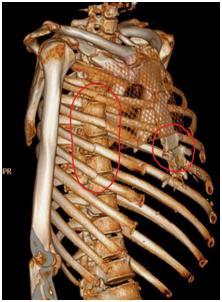

▲影像资料:术前肋骨三维重建 。

来自龙岗的李先生(化名)就是这一创新术式的受益者之一 , 今年1月 , 40岁李先生因为车祸受伤住进了龙岗中心医院胸外科 , 入院时伤情较重 , 相关检查提示双侧多发肋骨骨折 , 胸骨骨折 , 双肺挫伤 , 右侧血气胸 。 洪琼川主任团队迅速制定救治方案 , 经术前讨论后决定为李先生施行“胸腔镜下右侧肋骨骨折内固定、胸骨骨折内固定术” 。 由于患者右侧第3-6肋骨错位明显 , 术中给予记忆合金肋骨接骨板固定了错位肋骨 , 胸骨爪固定胸骨骨折处 。 手术过程顺利 , 术后经过抗感染活血促骨折愈合雾化排痰等治疗 , 复查胸部X线提示肋骨爪及胸骨爪固定良好 , 李先生住院一周后顺利康复出院 。